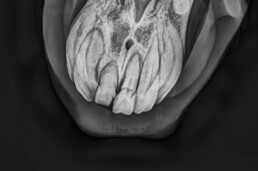

- röntgenologische Untersuchung zur Bestätigung der Verdachtsdiagnose EOTRH

- deutliche Befunde erkennbar

- resorptive und hyperzementotische Veränderungen an den Schneidezähnen/Schneidezahnwurzeln